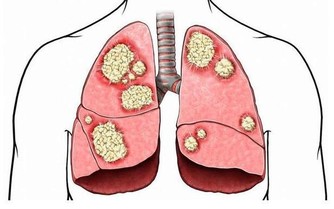

中醫稱認為失眠主要病位在心、腦,

與腎、肝、膽、脾、胃等臟腑相關,

若氣血陰陽失和、臟腑功能失調,

導致心神失養,或心神不安,均會引起失眠。

失眠危害大 記憶力衰退、反應遲鈍上身

千萬不要小看失眠,失眠的危害大,

睡眠不足的人容易感到疲勞、無精打采、

反應遲鈍、頭痛、記憶力衰退、

注意力不集中、脾氣暴躁,

也可能誘發高血壓、糖尿病、冠心病,

甚至會導致女性皮膚乾燥、

月經失調等症狀。